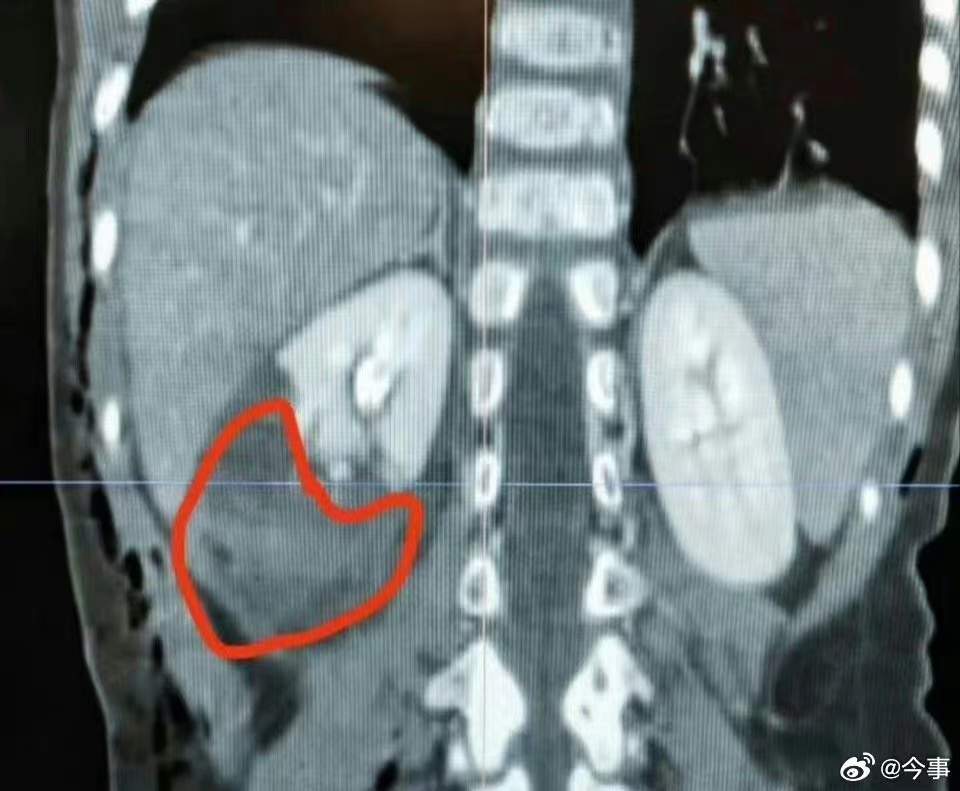

四川一小区内大狗撕咬2岁半小女孩,ct显示肾挫裂伤!伤口看着都吓人…

初步诊断还有肾挫裂伤

女童整个右侧有多达20多处的咬伤

最大的伤口有8公分

最严重的肾脏损伤问题

目前也只能暂时使用保守治疗

因为现在做手术

会很高的丢肾的风险